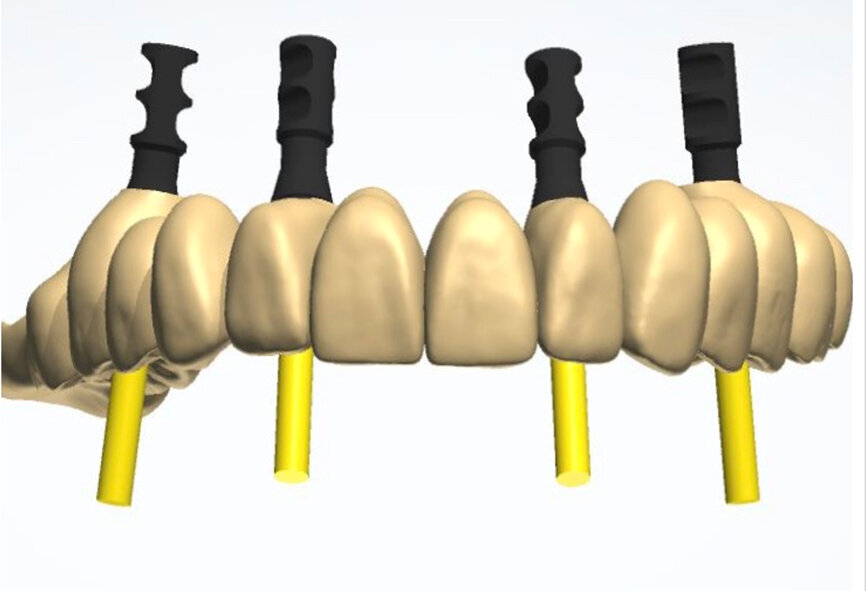

To design the prosthesis digitally, we first selected the screw-retained abutment (SRA) angle and gingival height (Fig. 14) and then we created the patient model on which we could connect the BLX implants with the SRAs selected from the Straumann library (Fig. 15). The implant placement guide was on the model, leveraging the high stability that we could gain from palatal support (Figs. 16 & 17). After printing the model, the BL  implant analogues were positioned using the template for navigation. The digital planning using coDiagnostiX (Version 9.14) allowed the dental technician to identify all the necessary parameters related to implant position (Figs. 18–22). Emergence profiles were set-up on the model (Fig. 23). The model was scanned using scan bodies, and a CAD/CAM temporary restoration was designed and milled in a PMMA-based restorative material (Figs. 24–29).